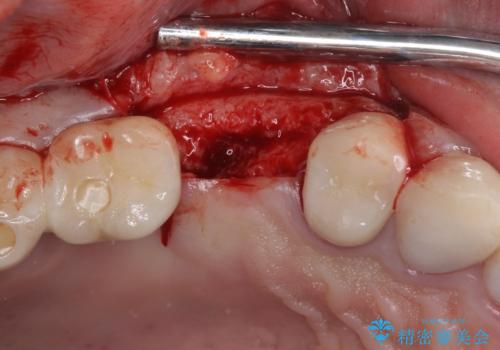

- 咬合力により歯が割れてしまった方のインプラント治療です。

抜歯後4ヶ月ほど待ち、後方のインプラントと同一メーカーのインプラントを埋入することとしました。

大変怖がりであるため、インプラント治療の際には静脈内鎮静により、眠っている間に手術を行いました。